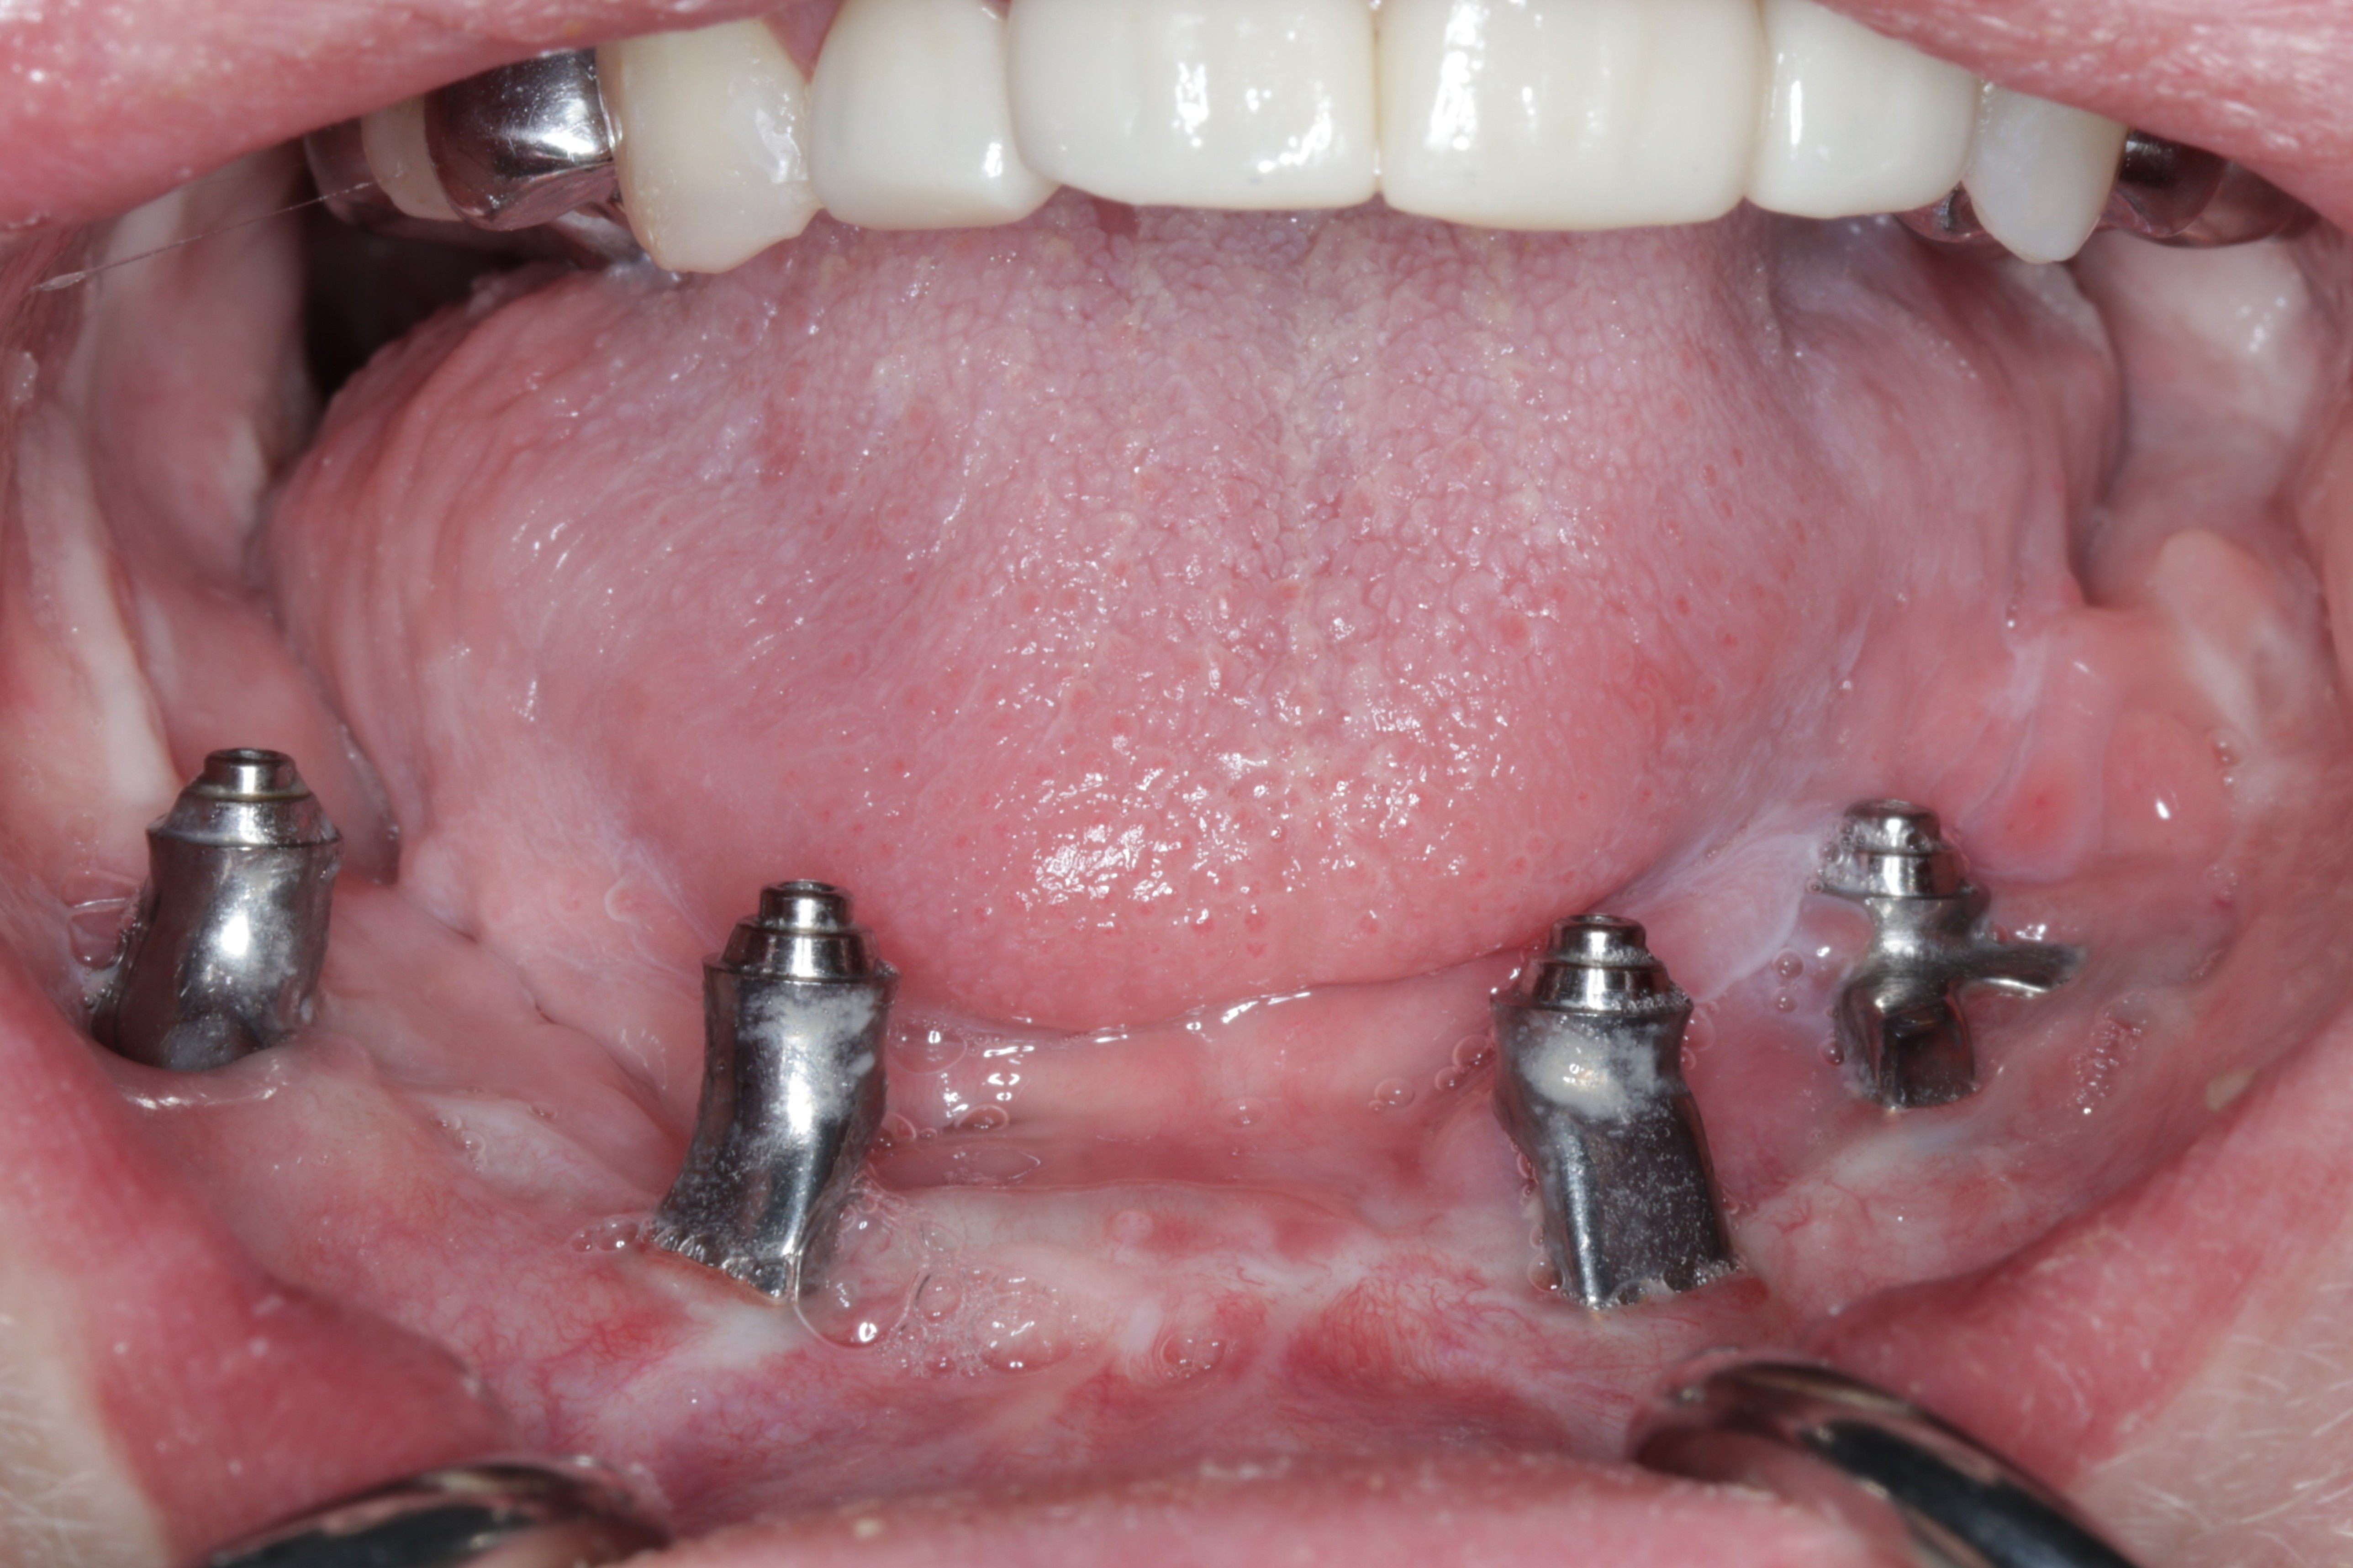

A custom occlusal splint confirmed mount and prosthetic space. The site was closed with resorbable sutures intraorally and plain gut at trocar sites. Recovery was uneventful, and the patient progressed to prosthetic rehabilitation (Figs 9 and 10).

The existing prototype was removed using an extra-short multi-unit abutment (MUA) prosthetic screwdriver (BioHorizons). The patient shifted his mandible laterally to permit access to posterior screw channels (Fig 11).